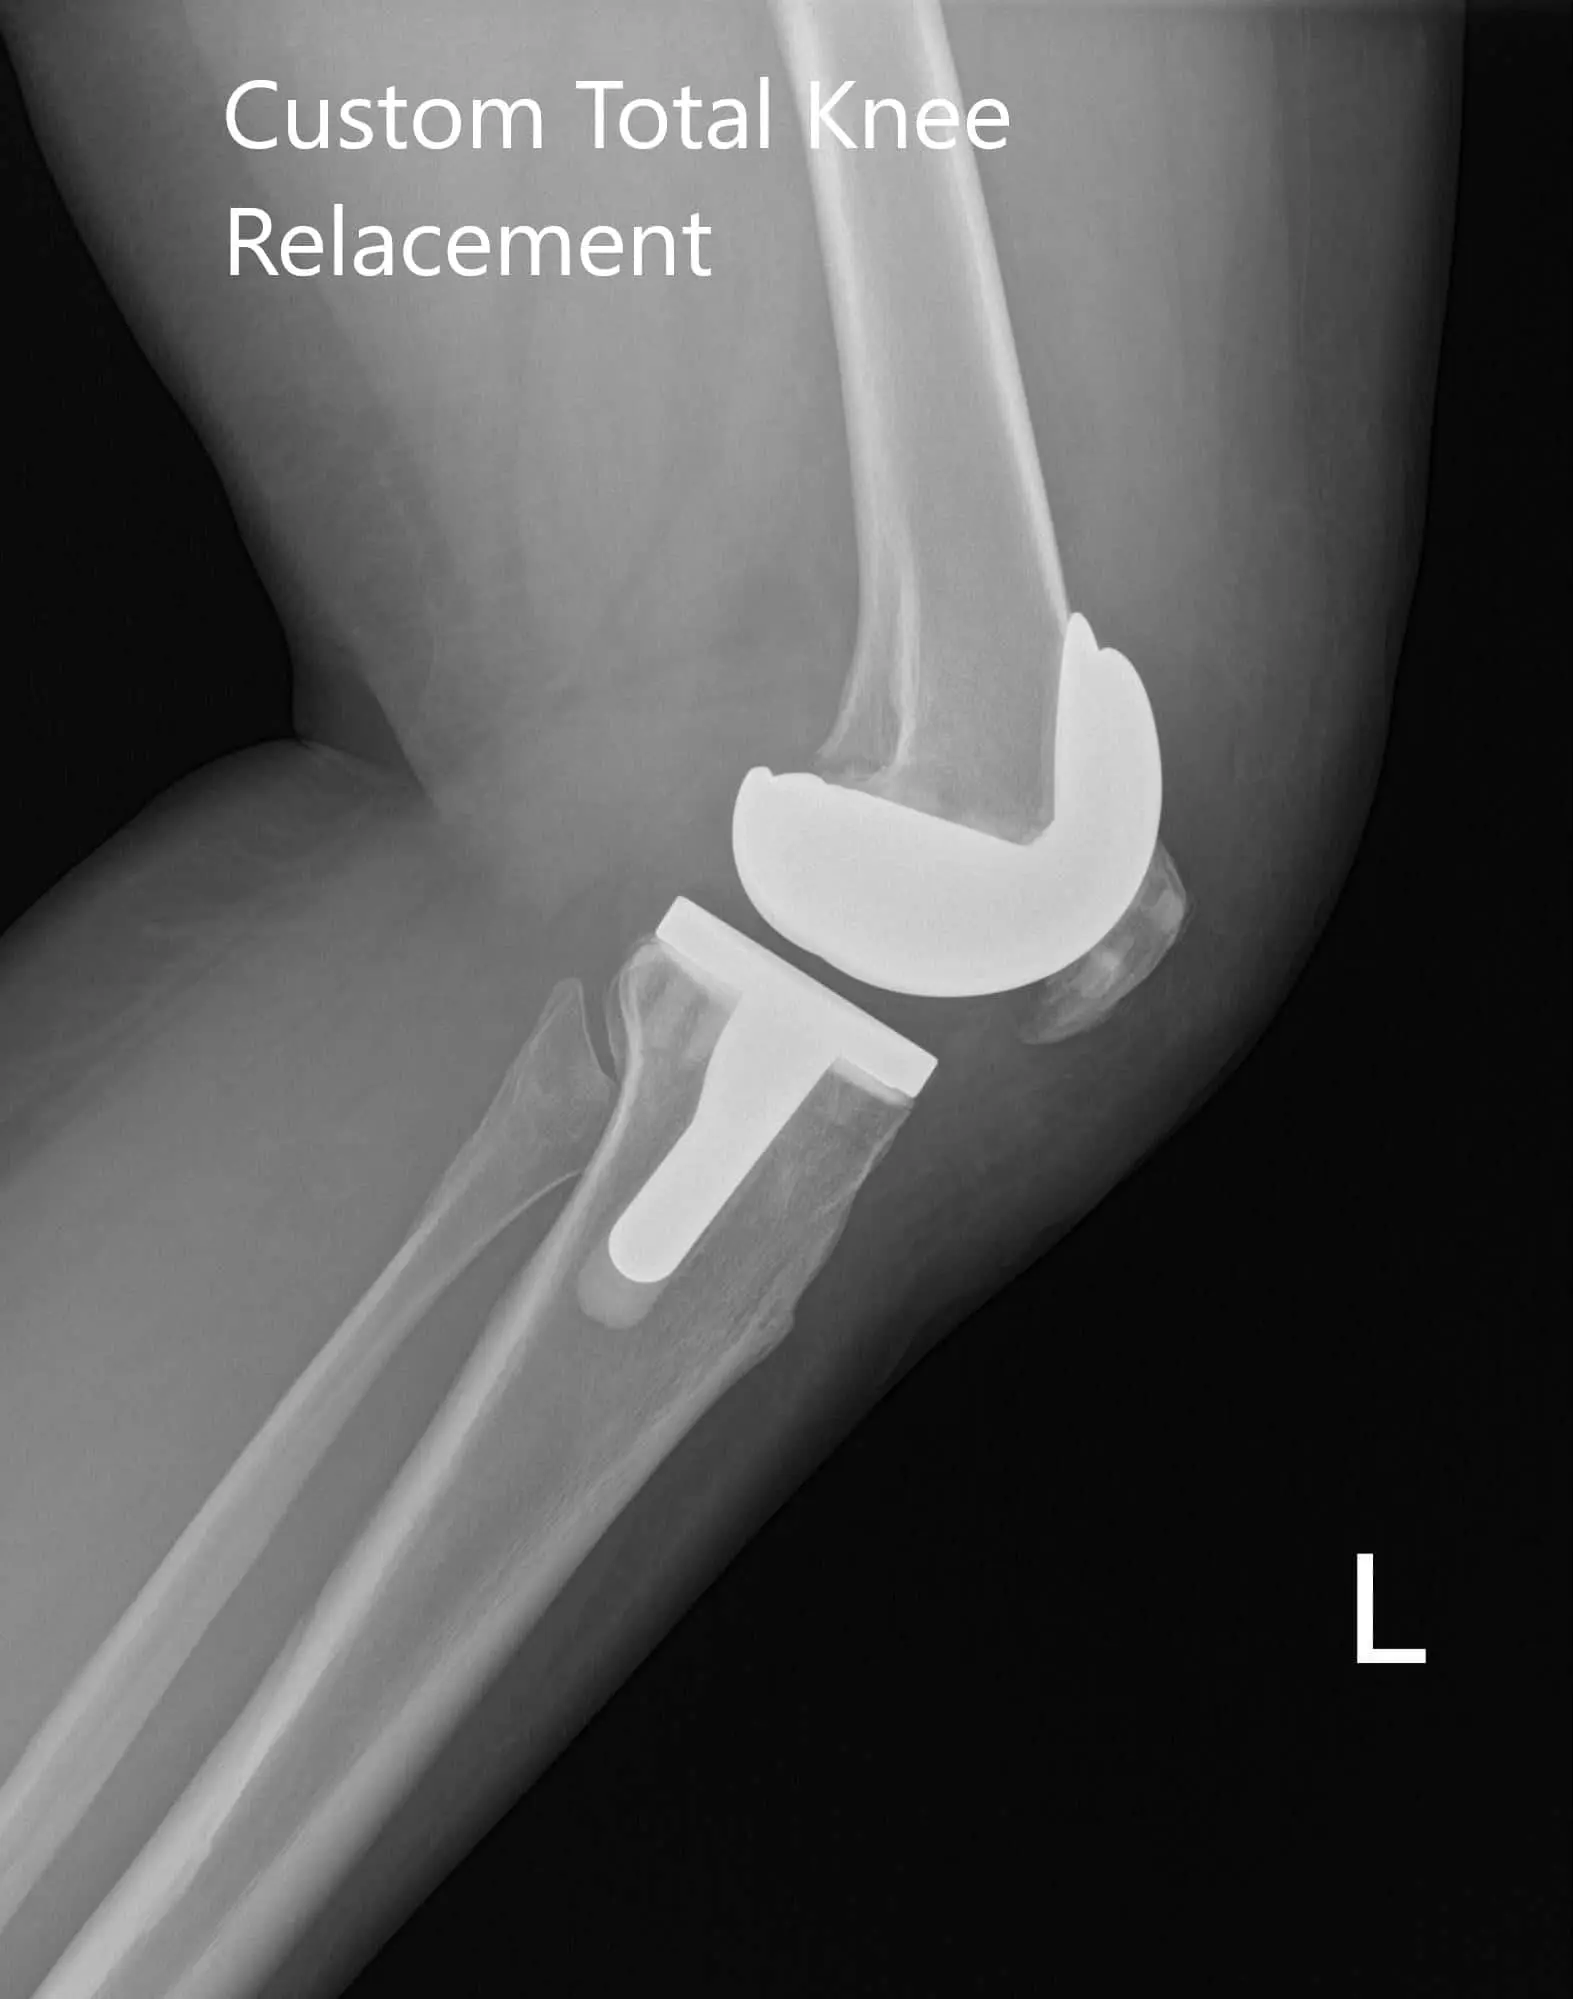

Postoperative X-ray of the left knee showing AP and lateral image

Postoperative X-ray of the left knee showing AP and lateral images - img 2

Postoperative X-ray of the left knee showing AP and lateral images

The patient was ambulatory the same day of the surgery. He reported well control of pain with medications and had a good range of motion about the left knee. The patient’s wound was clean, dry and intact. He had excellent compliance with physical therapy and home exercise program. He reported no pain (0/10) and an excellent range of motion after 3 months.